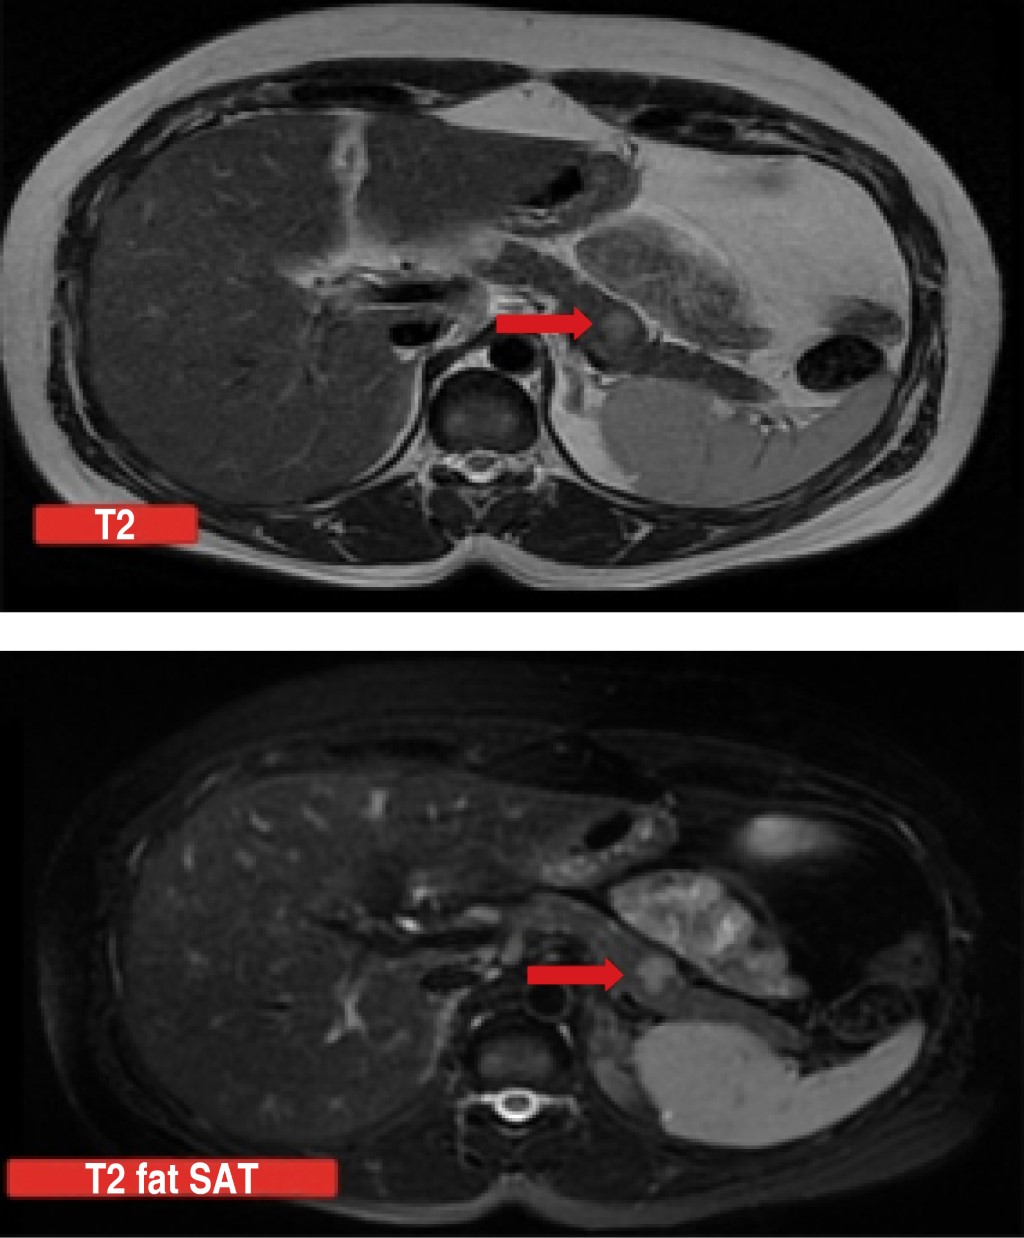

Due to severe and recurrent hypoglycemia not associated with the intake of antidiabetic or exogenous hypoglycemic agents, a 72-hour fasting test was performed with measurement of glucose and insulin levels, confirming hypoglycemia with normal insulin levels; a tomography of the skull and sella turcica was performed without finding lesions; However, an abdominal CT scan showed the presence of a focal increase in the size of the adrenal gland, so it was decided to characterize with MRI of the abdomen in which a single focal lesion of 13 × 10 mm was identified at the junction of the pancreatic body and tail (Figure 1), described as hypointense in T1 sequences fat saturation techniques (FAT SAT), slightly hyperintense in T2 sequences with discrete peripheral enhancement after contrast administration and restriction in diffusion-weighted magnetic resonance imaging (DWI) sequence and an apparent diffusion coefficient (ADC) map.

Figure 1